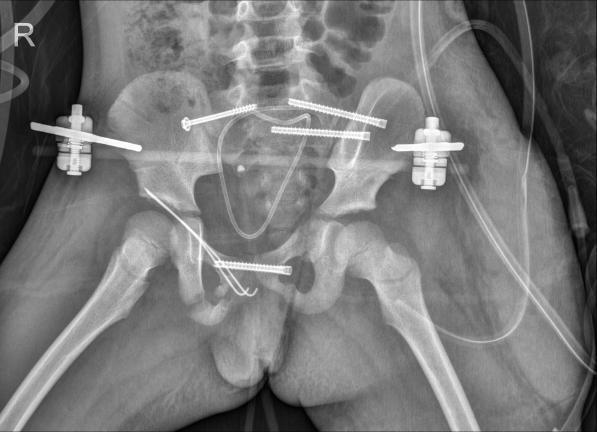

医生们仔细清理骨折部位间嵌插的软组织及凝血块,复位骨折部位,再用克氏针、空心钉等进行固定。为了保证治疗效果,他们还借助机器人导航技术,通过C形臂透视规划进钉位置和方向,在左右髋部外侧精准置入导针和空心螺钉。

樊仕才完成骨折内固定后,妇产科主任王雪峰上台为小花进行生殖道修复,细细缝合每一处裂伤和离断;紧接着,泌尿外科副主任医师罗新贵接力,为小花进行尿道修复。妇产科和泌尿外科的修复工作顺利完成后,樊仕才团队再次回到手术台,给小花置入外固定架固定针,连接外固定架,稳固骨折部位。

术后